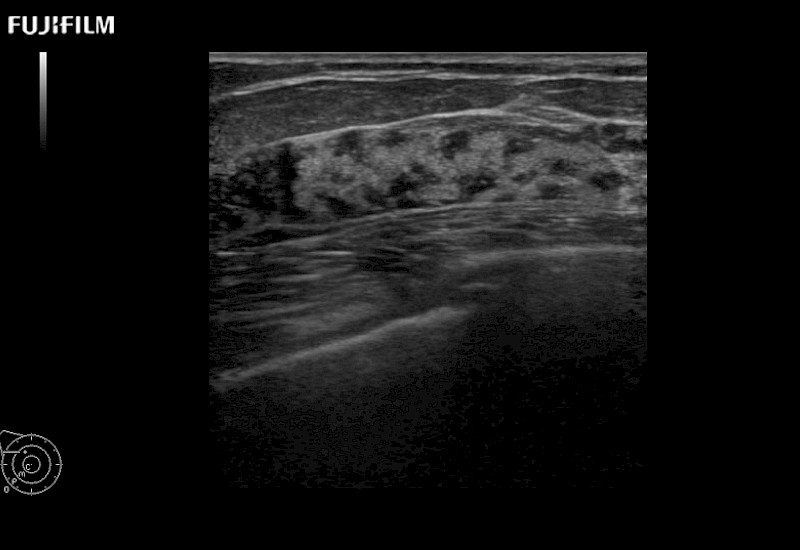

Extraordinary high-resolution digital imaging

Our dedication to Surgical Oncology allows us to offer superior image quality, outstanding system reliability and intuitive use of cutting edge technology.

- Exceptional near and far-field resolution

- Instant feedback on tumor margin delineation

- Valuable information to guide tumor resections

- Exceptional near and far-field resolution

- Instant feedback on tumor margin delineation